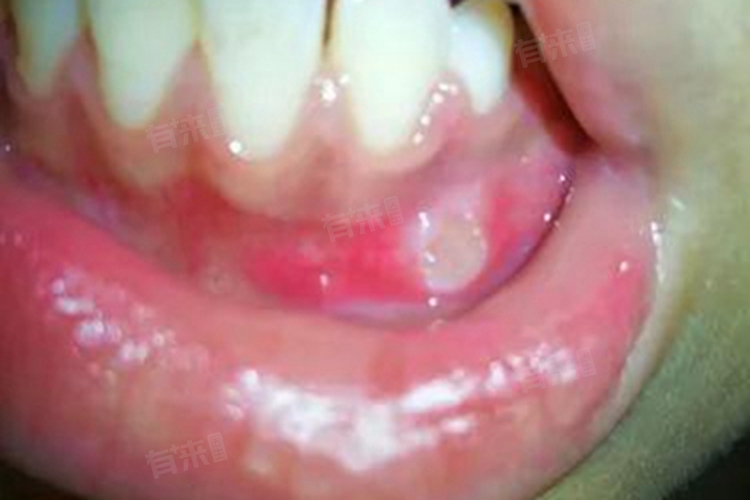

3、口腔溃疡:

当牙龈黏膜发生口腔溃疡时,初期可能表现为白色小点,周围伴有红晕。口腔溃疡的发生与局部创伤、饮食刺激、免疫因素等有关。白点处的黏膜上皮破损,下方组织暴露,受到冷热、辛辣等刺激时会产生疼痛,随着病情发展,白点可能扩大形成圆形或椭圆形的溃疡面,影响口腔正常功能。